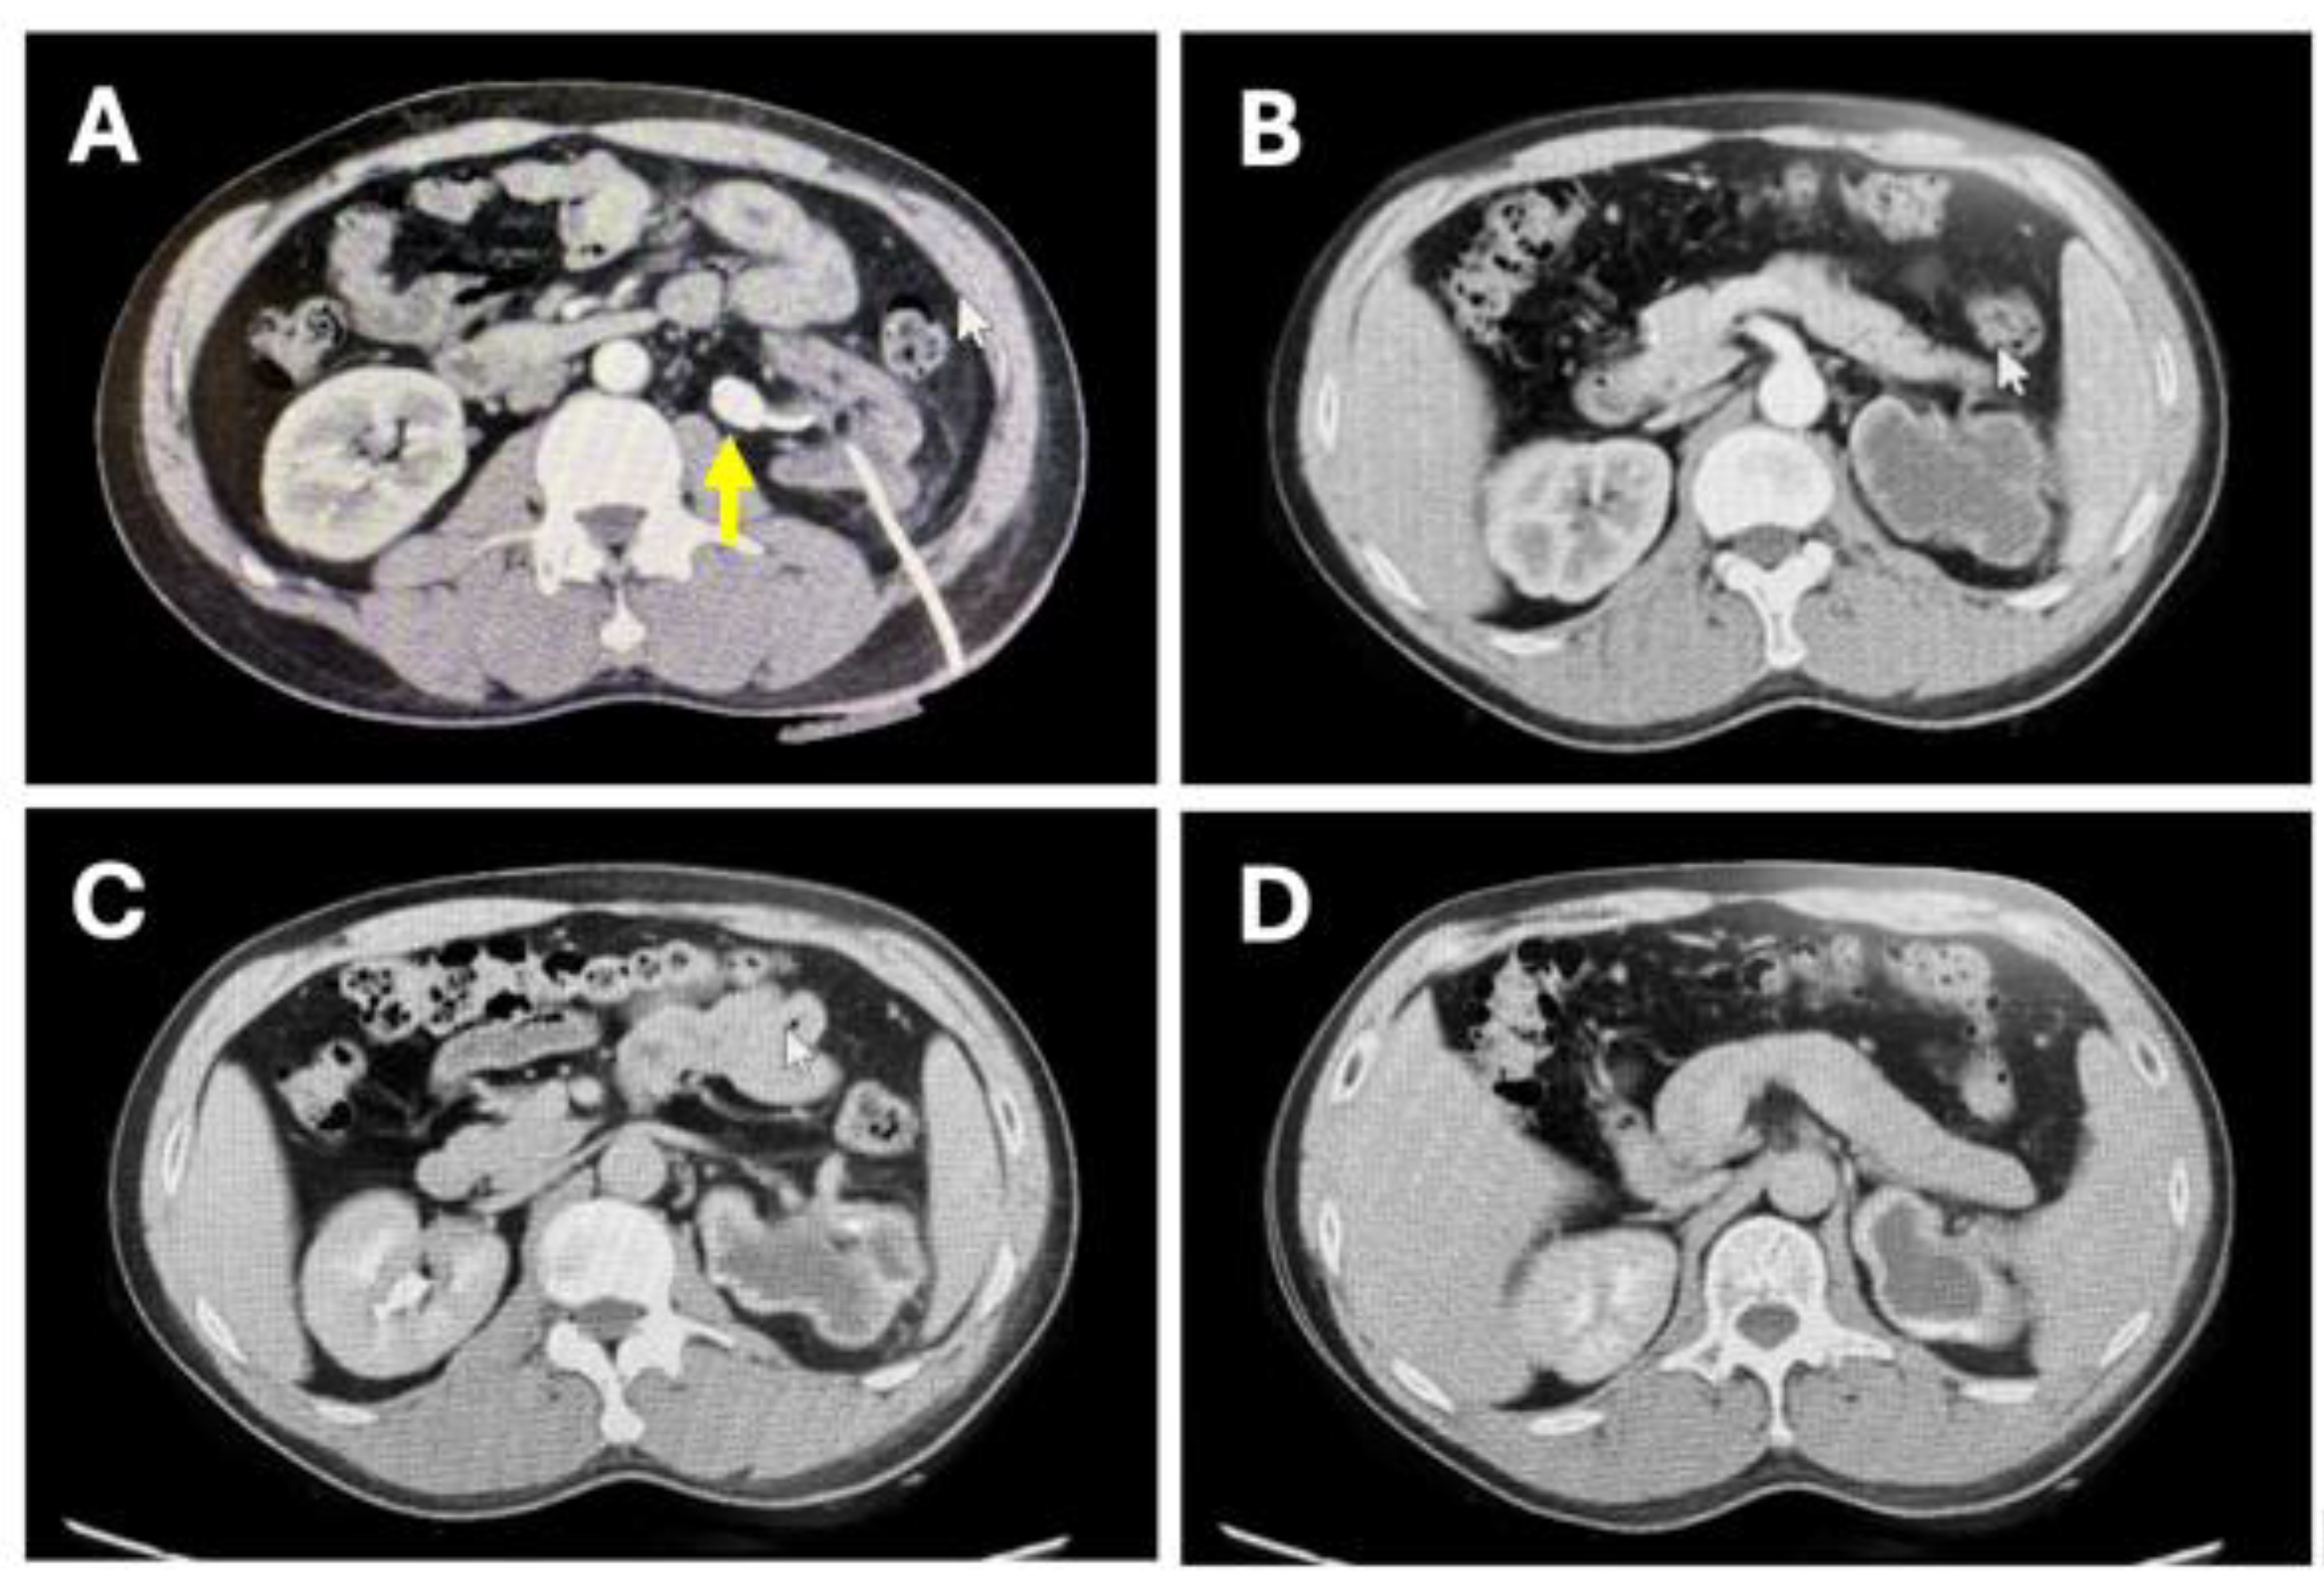

Figure 1. CT enhanced scan of the urinary system before surgery. (A) shows the left ureteral calculus and the position of the nephrostomy tube. (B) shows the thinning of the left renal cortex with poor enhancement in the arterial phase. (C) shows slight enhancement of the left renal cortex in the excretory phase, without contrast agent excretion in the renal pelvis. (D) shows a small amount of contrast agent excretion in the left renal pelvis in the excretory phase.

(1) Blood routine: White blood cells: 6.76*10^9/L (normal), neutrophils: 65.4% (normal), hemoglobin: 151 g/L (normal), platelets: 317*10^9/L (normal)(2) Blood biochemistry: Albumin: 46.4 g/L (normal), creatinine: 113 μmol/L (mildly elevated), blood urea nitrogen: 6.00 mmol/L (mildly elevated), uric acid: 477 μmol/L (mildly elevated), potassium: 4.0 mmol/L (normal)(3) Enhanced CT of the urinary system: Abnormal left kidney morphology, thinning of the parenchyma, percutaneous nephrostomy state; poor enhancement in the arterial phase of the left kidney, no significant enhancement in the renal pelvis during the excretory phase; calculus at the origin of the left ureter, size 1.8*1.3 cm, proximal left collecting system dilation and hydronephrosis, atrophy of the left renal parenchyma; multiple calculi in both renal calyces, the largest in the lower calyx of the left kidney, about 0.9*0.7 cm.